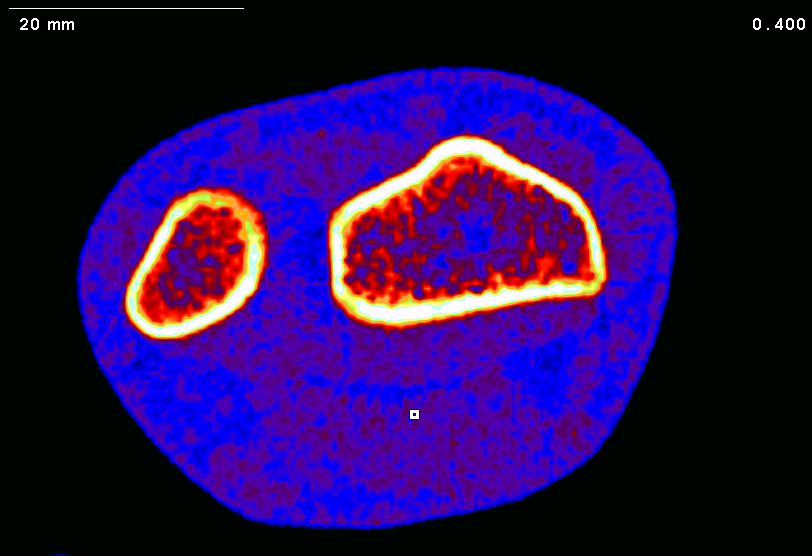

• *Denys AT, *Bugayong JC, *Juhala CC, *Ma EJ, *Carvalho KE, *Kwong SM, Yingling VR. Peak power and body mass as predictors of tibial bone strength in healthy male and female adults. J Musculoskelet Neuronal Interact. 2022 Jun 1;22(2):154-160. PMID: 35642695; PMCID: PMC9186462..[Preprint] SportRxiv.  https://doi.org/10.51224/SRXIV.1

• Yingling, V., *Reichert, R.,*Denys, A., *Franson, P., *Espartero, K., *Alvarez, M. ., *Huynh, K., *Serrano Vides, K., & *Mazzarini, A. (2021). Peak vertical jump power predicts radial bone strength better than hand grip strength in healthy individuals . Communications in Kinesiology, 1(2). https://doi.org/10.51224/cik.v1i2.13 (Original work published March 9, 2021)

• Yingling VR, Ferrari-Church B, Strickland A. 2018 Tibia functionality and Division II female and male collegiate athletes from multiple sports. PeerJ https://doi.org/10.7717/peerj.5550

• Yingling, V. R.; Webb, S.; Inouye, C.; O, J.; Sherwood, J. J. Muscle Power Predicts Bone Strength in Division II Athletes. J Strength Cond Res 2017, 1657–1665. https://doi.org/10.1519/JSC.0000000000002222

Bone strength prediction using field tests

Bone strength development